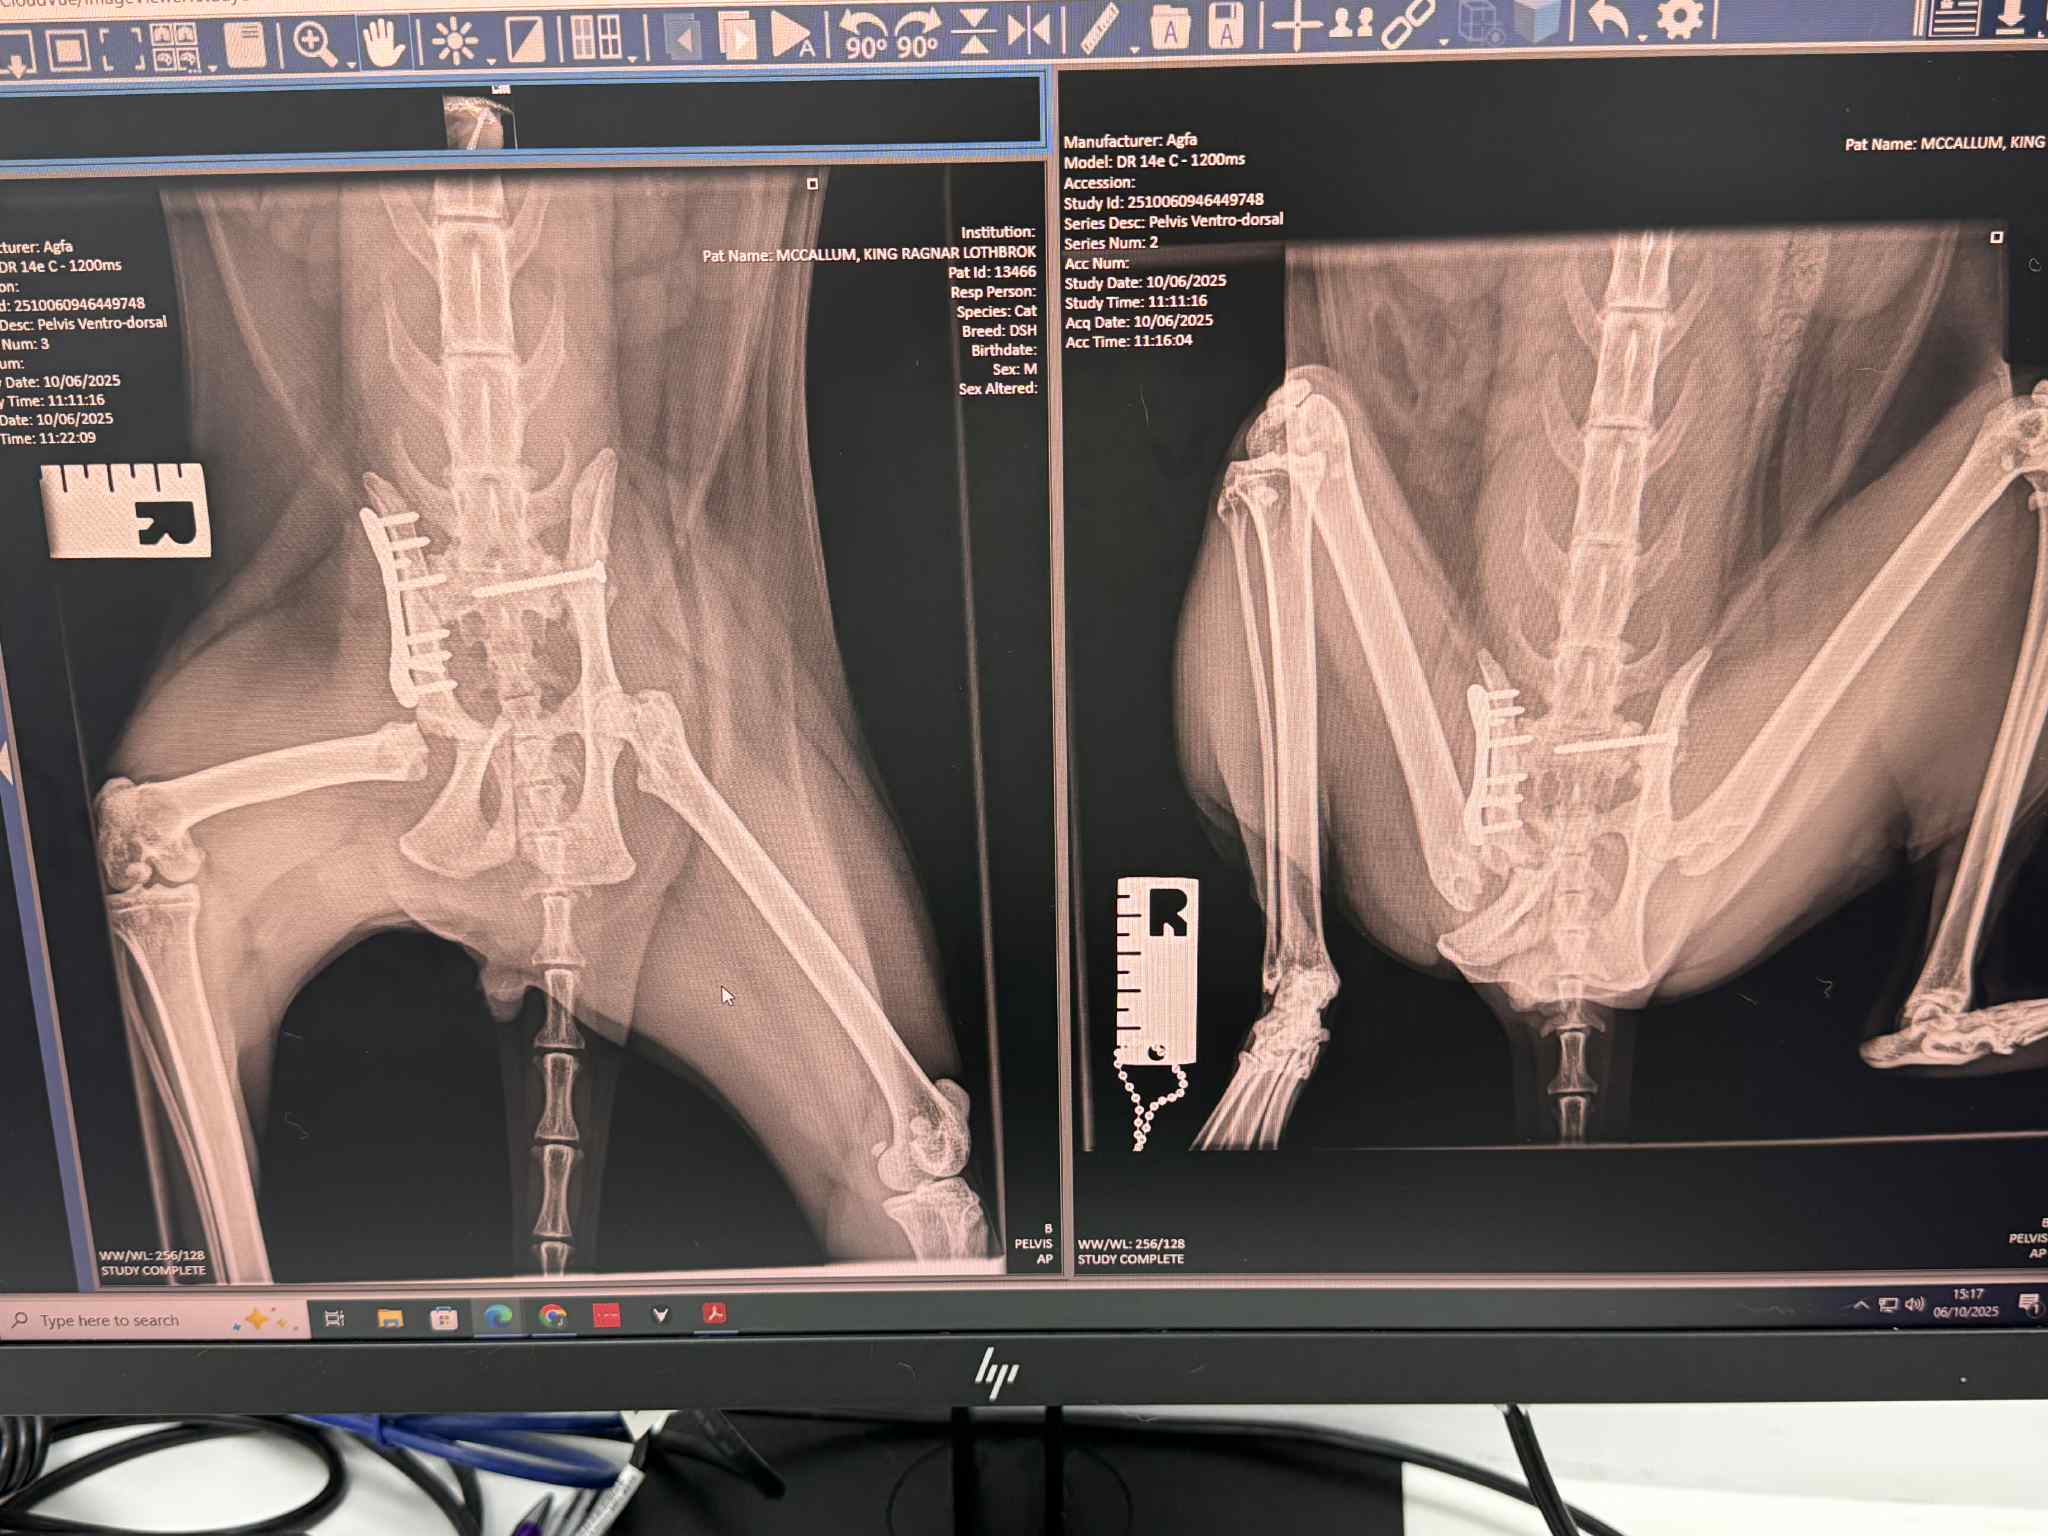

Monday was a long day. I spoke to vet who was going to operate first thing on Monday, and she explained the surgical plan for the day. She planned to put a screw in one side to pin the pelvis at that side to Ragnar’s sacrum. At the other side where the damage was worse, she proposed to plate and pin the top part of his pelvis but as the socket for his hip joint had been destroyed, she would also need to remove the head of his femur to allow the leg to sit in the correct position and give him the best chance of good use of it. The vet estimated that it would take her five hours in theatre.

Last week we took him back for his follow up appointment. He was to be sedated again to allow the vet to remove the temporary wire that had been fixating his jaw fracture and also to take a fresh set of x-rays. The good news when we collected him a few hours later was that everything is healing well. He was duly discharged from their care on the caveat that he be kept on partial cage rest for a further four weeks to allow the healing to continue and we were shown how to do some basic physio with him to help with the muscle wastage on the weaker side.